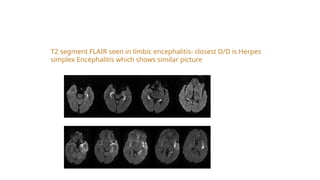

MRI of limbic encephalitis

T2 segment FLAIR seen in limbic encephalitis- closest D/D is Herpes

simplex Encephalitis which shows similar picture

MRI of limbicencephalitis

T2 segment FLAIRseen in limbic encephalitis- closest D/D is Herpes simplex Encephalitis which shows similar picture